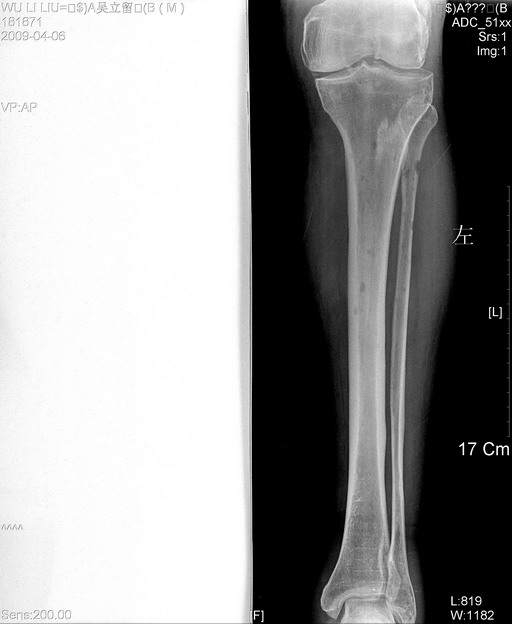

以下是引用zjzjr在2009-4-7 12:13:00的发言:[br]支持多发性转移瘤,右股骨颈骨折,腰椎亦有压缩性骨折.肝内胆管结石伴胆内外胆管扩张,左肾结石.

以下是引用liaoqiang在2009-4-7 8:44:00的发言:[br]考虑多发性骨髓瘤伴肝肺转移、肝内胆管结石、左肾结石、右股骨颈骨折。

以下是引用余辉在2009-4-7 8:52:00的发言:[br]椎骨及骨盆骨质疏松,骨破坏主要累及椎体,各骨破坏较广泛,各病灶边缘均较清晰锐利,血沉增快,白细胞增高.支持考虑多发骨髓瘤,建议查本尿周氏蛋白.[br]胆内胆管及左肾结石[br]右股骨颈骨折,考虑病理性